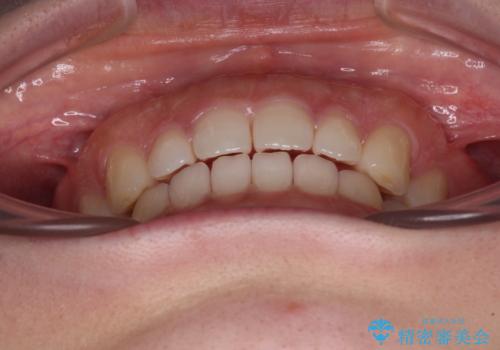

すきっ歯とオープンバイト インビザライン・ライトで改善

オープンバイトのため、奥歯に負担のかかる咬合状態であったので、矯正治療を提案したところ、希望をされました。

すきっ歯程度の軽度の歯列不正であったため、インビザライン・ライトにより咬合改善を行うこととしました。

オープンバイトやすきっ歯は、舌突出癖によりあっという間に後戻りをするため、矯正治療前からトレーニングを行っていただき、更には後戻り防止のワイヤーリテーナーを併用しています。